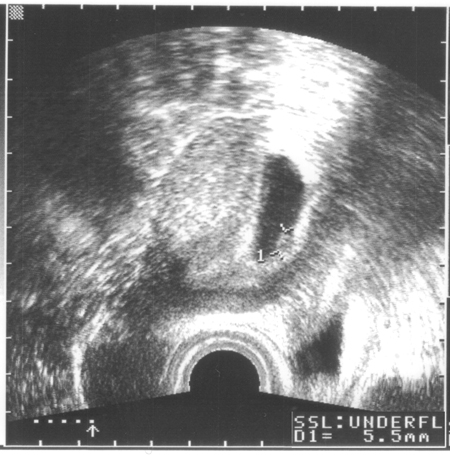

- ca. 17. April 2006

Bienchen und Blümchen ...

- 27. April 2006

Lange Debatte über eine feine Linie... Einer sagt "positiv",

einer sagt "negativ"

- 29. April 2006

Keine Debatten mehr dank eines dicken "+"

- 14. Mai 2006 ... Mamma is schon wieder echt übel ...